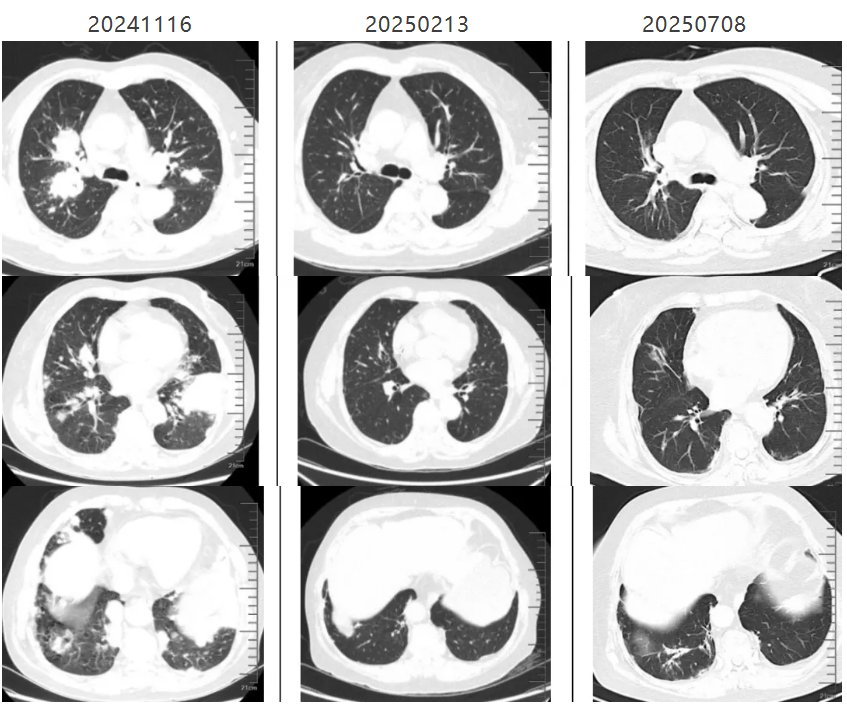

经治疗后,上述症状缓解不明显,主要症状为剧烈咳嗽、咳痰。遂复查胸部CT,提示双肺病灶较前进展。于2024年11月15日就诊于我院慢性咳嗽门诊,拟“双肺病灶 感染?肿瘤?”收治入院。

入院复查鼻窦+胸部CT提示:1、双侧上颌窦少许炎症 2、考虑左上肺前内基底段肺癌并两肺、胸膜多发转移,两肺门、纵膈淋巴结转移。3、左侧胸腔少量积液。

图4:胸部CT:双肺病灶抗感染治疗后仍进展

鼻窦+胸部增强CT:1.考虑左上肺前内基底段肺癌并两肺、胸膜多发转移,两肺门、纵膈淋巴结转移。2.左侧胸腔少量积液。3.双侧上颌窦少许炎症。

最终诊断为:弥漫大B淋巴瘤。诊断明确后,患者转入血液科进行下一步的治疗,治疗3周期后复查胸部CT提示病灶较前明显吸收,咳嗽症状明显好转。

图9:经淋巴瘤规范治疗胸部病灶明显吸收